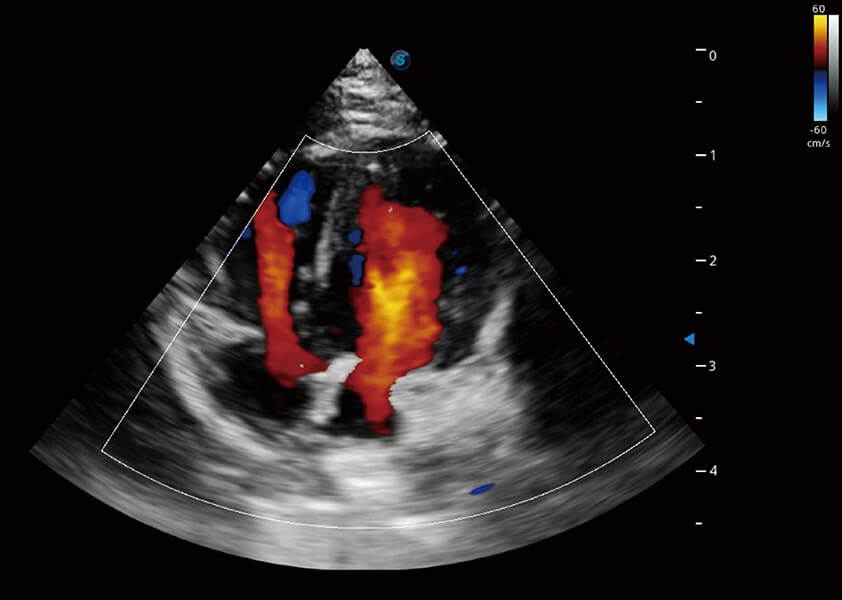

心脏解决方案

ProPet 60 配备了丰富的心脏探头群、先进的成像技术和专业的心脏测量工具,可帮助动物医生为不同体型和生理结构的动物提供心脏和心肌功能的全面评估。

优异的基础图像

(犬)四腔心血流